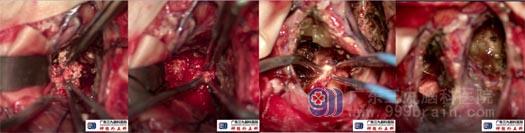

取原切口开颅,先沿着前纵裂分离,切除三脑室和鞍上肿瘤,可见肿瘤质地坚硬,钙化并包绕大脑前动脉,给予分块切除,直达鞍区;然后在额上回近纵裂处皮层造瘘切除左侧额叶及侧脑室内肿瘤,极少部分肿瘤与前交通动脉复合体黏连紧密,难以切除。